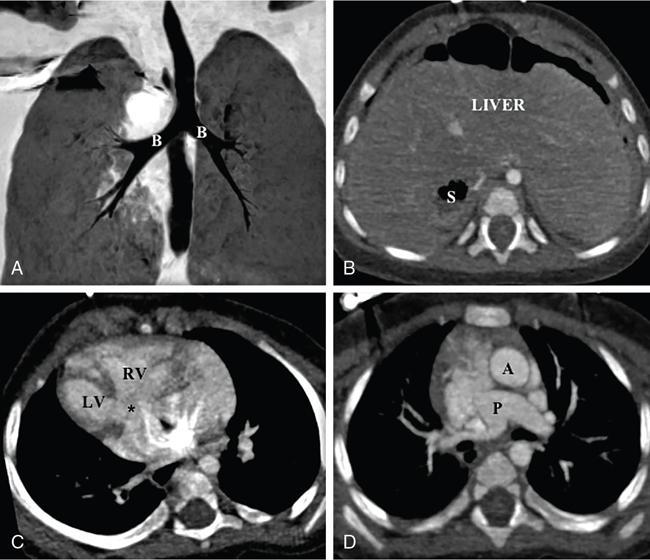

Kalpana Bansal, Poonam Narang The paediatric splenic abnormalities include both congenital and acquired pathological conditions. The congenital anomalies include variations in splenic number, location or fusion abnormalities and are more common than the acquired pathological conditions like splenomegaly, focal lesions, tumours and trauma. The splenic pathology can be evaluated with a wide variety of available imaging modalities including an ultrasound that is usually the first modality of choice in paediatric patients, computed tomography, magnetic resonance imaging and technetium-99m scintigraphy. The pattern-oriented approach to the radiological evaluation of splenic abnormalities may help to reach an accurate diagnosis and plan patient management. The congenital anomalies are common splenic abnormalities in paediatric patients. They usually result from absent or incomplete fusion of splenic lobules into one single organ before birth or abnormal location of the spleen. The congenital malformations include: The accessory spleen is commonly referred to as the splenunculus or supernumerary spleen. It results from the failure of the fusion of the primordial splenic buds in the dorsal mesogastrium during foetal life. The incidence is seen in 10%–30% of the population. The most common location of an accessory spleen is near the splenic hilum seen in about 75% of the cases and the pancreatic tail in 25% cases. It may be located anywhere along the course of the splenic vessels or in the abdomen and pelvis. The size of an accessory spleen ranges from few millimetres to centimetres and the number may vary from 1 to 6 (Fig. 9.21.1). The accessory spleens are usually asymptomatic and incidentally detected on imaging. But an accessory spleen present in an unexpected location can be misinterpreted as an abnormal soft tissue mass or lymph node. The characteristic imaging findings of the accessory spleen include similar imaging appearance to normal spleen on CT and MRI. The demonstration of feeding artery from the splenic artery can also be helpful in the differential diagnosis. Iron-containing MR contrast agents and Tc-99 sulphur colloid scintigraphy may be useful to confirm the diagnosis. The clinical significance of accessory spleen is seen in patients who had splenectomy for hypersplenism. In such patients, the accessory spleen may hypertrophy and result in recurrent disease; however, in patients of splenic trauma who had a splenectomy, it may help preserve the immune functions of the spleen. Splenopancreatic fusion is a rare anomaly that results due to abnormal fusion of splenic or pancreatic tissue as both organs arise from the dorsal mesogastrium close to each other. The ectopic splenic tissue may be located in the pancreatic tail (Fig. 9.21.2) and ectopic pancreas in the spleen or accessory spleen. It is also an incidental finding and asymptomatic. The clinical importance is to avoid complications during splenectomy or distal pancreatectomy. Splenogonadal fusion is an extremely rare anomaly that results due to the persistence of splenic tissue between the spleen and left testicle or epididymis. It may simulate masses and warrant unnecessary surgeries. The demonstration of splenic tissue connecting the spleen with the left gonad using any of the imaging modality helps in definitive diagnosis. Wandering or ectopic spleen is an extremely rare entity that results due to laxity or maldevelopment of the supporting splenic ligaments, and spleen can be found in any part of the abdomen. The incidence in several large studies of splenectomy is less than 0.5% and is mainly seen in children. The wandering spleen may be detected incidentally or present with different degrees of abdominal pain related to intermittent or acute torsion of the vascular pedicle. Ultrasound and CT remain the mainstay of diagnosis. Imaging findings include the absence of spleen in its normal position and a mass located anywhere in the abdomen or pelvis showing imaging and enhancement characteristics of normal splenic tissue. Besides, in the case of torsion, a typical ‘whirl’ pattern of the twisted pedicle and altered enhancement may also be demonstrated. Doppler shows absent flow within the spleen and low diastolic velocity with raised resistive index in the proximal splenic artery. The unenhanced CT shows hypoattenuation of the spleen, hyperdense intraluminal thrombus in the splenic artery and high density of the splenic capsule relative to parenchyma (‘rim’ sign). The contrast-enhanced CT shows absent or heterogeneous enhancement. The treatment modality of choice is splenopexy; however, splenectomy may be indicated in cases of infarction. Polysplenia and asplenia are typically seen in association with situs ambiguous or heterotaxia. Situs ambiguous with asplenia also known as Ivemark syndrome refers to right isomerism or bilateral right-sidedness and is characterized by an ambiguous location of abdominal organs with congenital absence of the spleen. It is more prevalent in males and associated with congenital heart disease in almost all cases (Fig. 9.21.3). Most patients die within the first year of life due to associated severe congenital heart disease and immunodeficiency due to absent spleen. Situs ambiguous with polysplenia is referred to as left isomerism or bilateral left sidedness. It is more common in females. The spleen may be located on the left or right side of the upper abdomen, the number may vary from 2 to 6 and diameter ranges from 1 to 6 cm (Fig. 9.21.4). The coexisting anomalies include a right-sided stomach, a midline or left-sided liver, bowel malrotation, short pancreas, absent gallbladder and associated inferior vena cava anomalies. Splenosis is an acquired anomaly that occurs following splenic trauma or splenectomy. It results due to auto-transplantation of splenic tissue usually in the peritoneal cavity but also may occur in extraperitoneal locations like the thoracic cavity. Splenosis is usually asymptomatic and incidentally detected on imaging. Splenosis is an acquired condition so it has distorted architecture and is supplied by surrounding vessels so, it can be mistaken for neoplastic lesions and lead to unnecessary surgery. A patient who had splenectomy for hypersplenism, splenosis may result in recurrent disease. However, a functioning splenic tissue may be required to preserve normal immunological function and remove old blood cells. Splenomegaly is a nonspecific finding seen as a manifestation of various disease processes listed in Box 9.21.1. CAUSES OF SPLENOMEGALY Ultrasound is usually the first and useful modality to evaluate enlarged spleen. It accurately measures the splenic span and also assesses the splenic echotexture, homogeneous or heterogeneous. Doppler USG is very good for the assessment of portal hypertension as a cause of splenomegaly by demonstrating flow in the splenoportal axis and collaterals. Both USG and CT also assesses the ancillary findings like lymphadenopathy in case of lymphoma or tuberculosis. Portal hypertension is one of the most common noninfectious causes of splenomegaly in children. Patients usually present with significant gastrointestinal bleed or massive splenomegaly. The causes of portal hypertension may be prehepatic, intrahepatic or posthepatic. The portal vein thrombosis is mostly idiopathic in children and results in collateral vessel development at porta known as cavernous transformation of the portal vein or portal cavernoma and portosystemic collaterals with massive splenomegaly (Fig. 9.21.5).